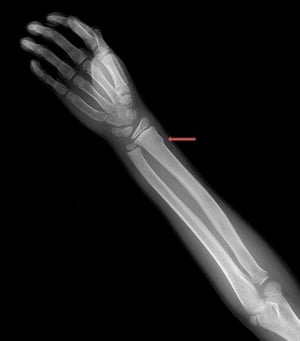

Компресійний веретеноподібний перелом зап'ястка

Такий компресійний веретеноподібний перелом дистального відділу променевої кістки візуалізується лише у вигляді незначних нерівностей кіркового кісткового шару.

LIVING ART ENTERPRISES, LLC/НАУКОВА ФОТОБІБЛІОТЕКА